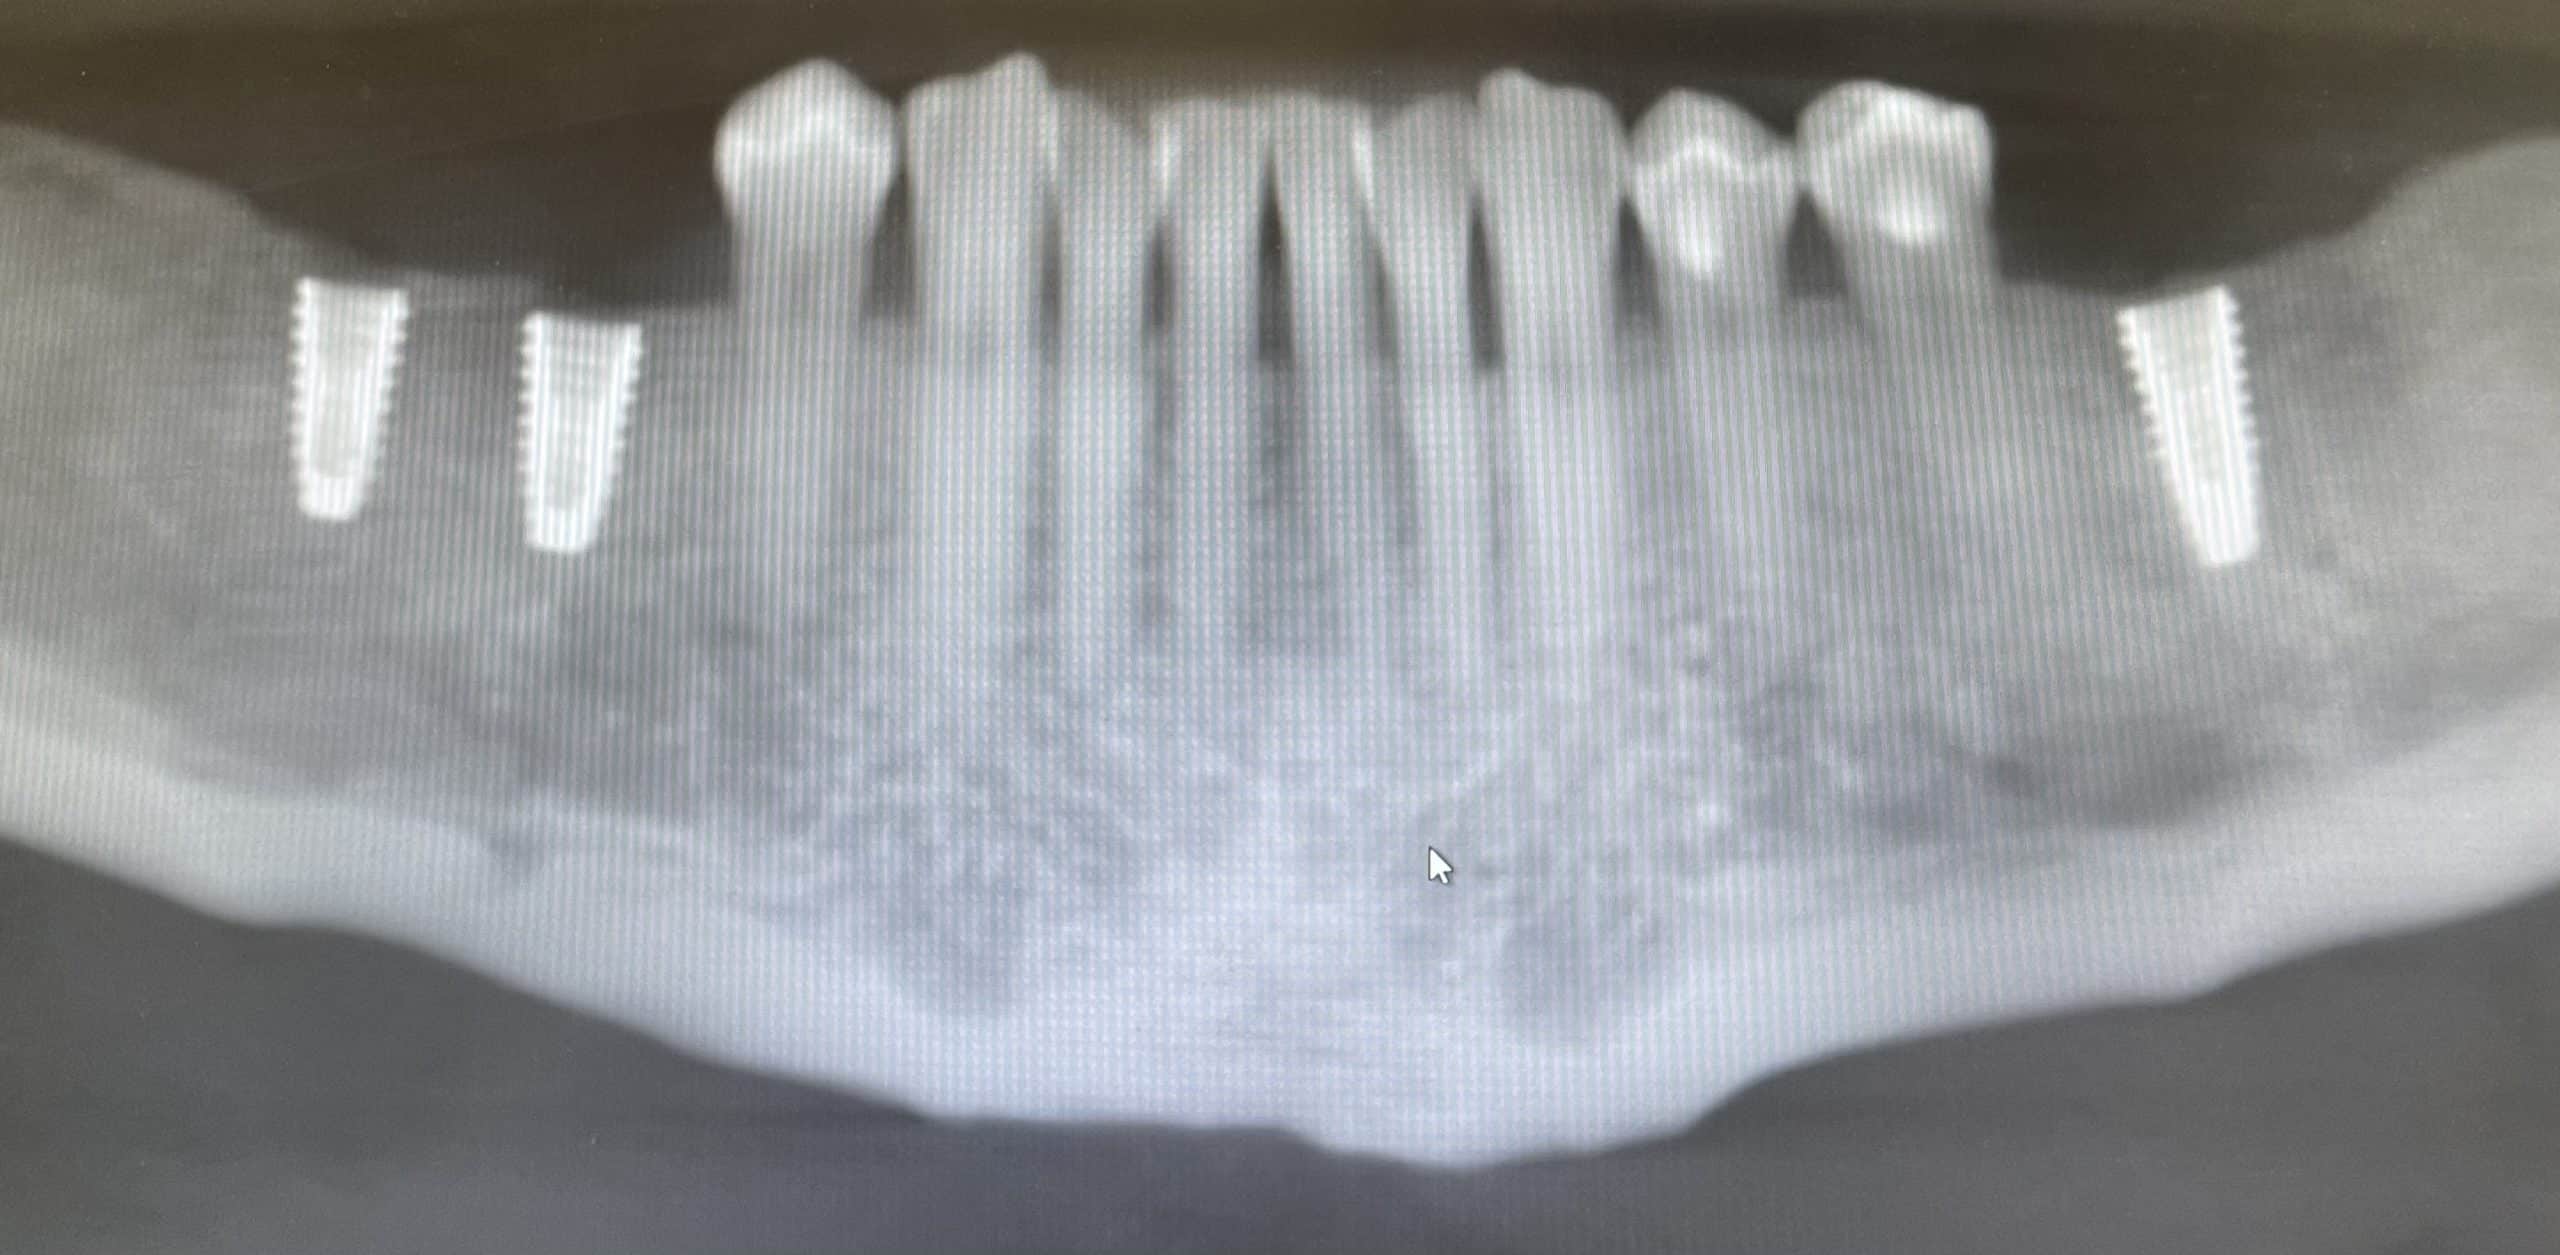

We will perform a thorough oral evaluation and use the most advanced dental technology to fully diagnose and customize your new smile design. Digital imaging (known as a CT scan) captures accurate intraoral data of your entire mouth. From there, detailed plans are designed, created and revised. Once finalized, the prosthetic design and surgical guide are fabricated.

On the day of your implant placement, your personalized surgical guide is used to accurately position the implant with sub-millimeter accuracy. The surgical procedure is amazingly quick and painless. A healing cover is then placed on top of the implant which allows the implant and tissue to heal.